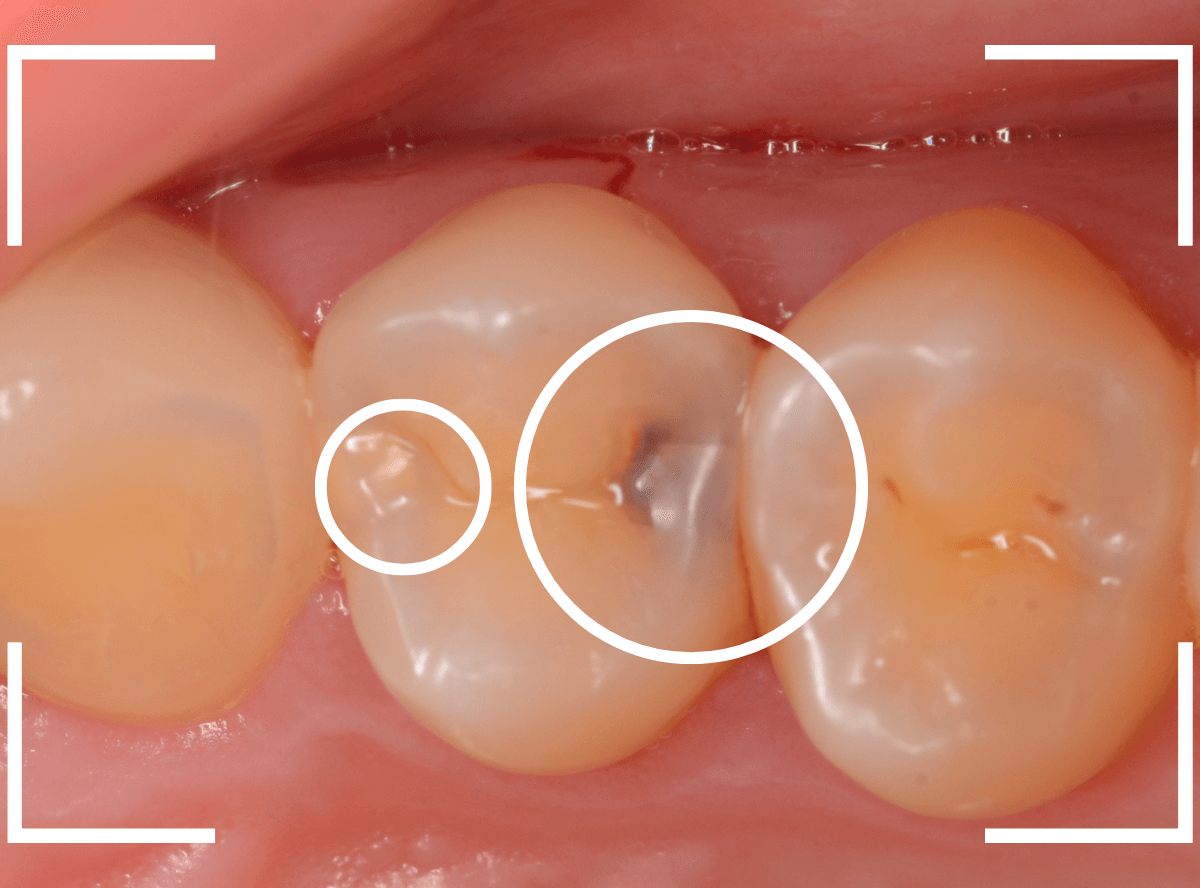

Case.7 定期メンテナンスで虫歯を発見!

メンテナンス時に、虫歯がみつかった患者さんです。

奥(右の〇)側が黒く虫歯が透けて見えますね、割とわかりやすい隣接面う蝕です。

よく見ると手前(左の〇)側も中が白濁してう蝕らしくなっているのがわかります。

レントゲン写真で確認します。

奥側の虫歯は明らかにレントゲンでも確認できますね、手前側の虫歯ははっきりしません。